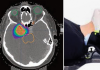

[제주, 제주인의 건강보고서 Ⅷ 건강다이어리] (162) 방사선 치료

절개 없이도 암 완치 목표 치료호흡에 따른 장기 움직임 분석치료 효과 높이고 합병증 줄…